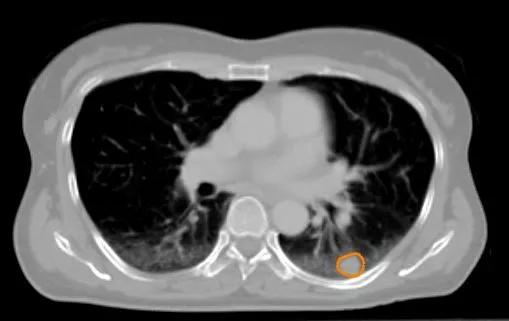

Vand i lunge

To scanningsfotos af den samme lungekræftpatient, der viser, hvor meget anatomien kan ændre sig:

Tværsnit af brystkassen hos samme patient, efter at der er kommet vand i lungen. Svulsten ligger nu oven på væsken - den oprindelige placering er markeret med orange.